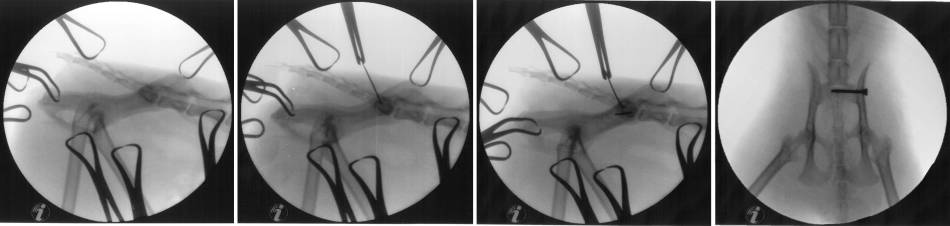

Minimalinvasive Reposition

- perfekte Seitenlage in Vakuummatratze (Proc. transversi superimposed)

- Reduktion der Fx

- cranial Dornfortsatz L7 angklemmen

- caudal Ilium / Sitzbein anklemmen

- Ilium nach caudal drücken

- nach Reduktion kleinen Pin setzen caudal davon wo die Schraube gesetzt wird

- Bohrung für Positionsschraube

- erst Pin setzen um für Bohrung vorzubereiten

- Hautschnitt und bis zum Ilium präparieren

- Bohrhülse über Pin stecken

- Pin entfernen und bohren

- Gleitloch bohren (vor OP schon Tiefe durch Ilium messen

- Schraube setzen

- Zugschraube 2,7 mm

- soll über mind. 60% des Sakrums gehen (Schraube ggr. kürzer als Bohrloch, evtl. Beilagscheibe nehmen)